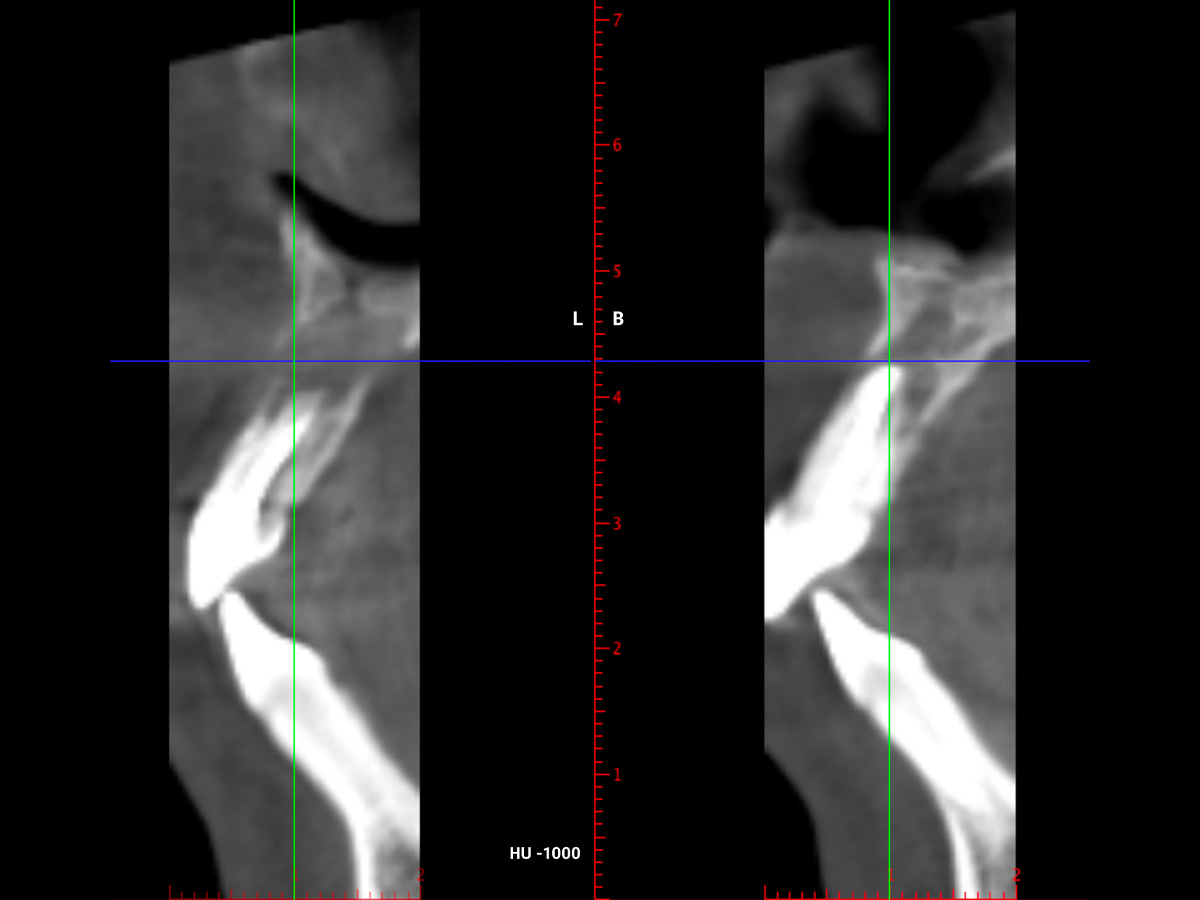

Nach einem Zahntrauma im Jugendalter mit anschließender endodontischer Versorgung stellte sich unsere 24-jährige Patientin mit seit einigen Monaten bestehendem, rezidivierendem Druckgefühl und leichten Schmerzen in regio 11 und 12 vor (Abb. 1, 2, 3). Die klinische Untersuchung ergab an Zahn 11 und 12 Lockerungsgrad 1 und, wie zu erwarten, eine negative Sensitivität. Es lag ein leichter Perkussionsschmerz vertikal wie horizontal vor. Die Krone auf Position 11 zeigte eine leichte Verfärbung im Vergleich zu den Nachbarzähnen. Ein OPG ergab eine – in ihrer Ausdehnung nicht sicher zu beurteilende – Aufhellung im Knochenbereich regio 11 und 12 (Abb. 4). Als Nebenbefund waren teilretinierte Zähne 38 und 48 sowie ein vollständig retinierter Zahn 28 als Mikroform nachzuweisen. Ein zusätzlich durchgeführtes DVT zeigte eine große zystische Formation unter Einschluss der Wurzeln 11 und 12, die vom Canalis nasopalatinus bis mesial 13 mit einer kleineren Perforation zum Nasenboden und größeren Perforationen nach vestibulär und palatinal reichte (Abb. 5, 6, 7).

Abbildung 5

Im DVT ist eine große zystische Formation unter Einschluss der Wurzeln 11 und 12, die vom Canalis nasopalatinus...

Abbildung 6

...bis mesial 13 mit einer kleineren Perforation zum Nasenboden...

Abbildung 7

...und größeren Perforationen nach vestibulär und palatinal reicht.